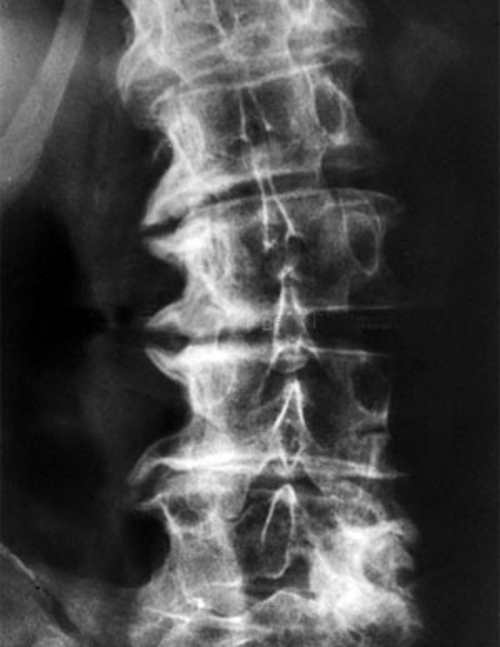

Диагноз “деформирующий спондилез” устанавливается на основе рентгенографического исследования позвоночника. Рентгеновские снимки позволяют оценить степень и распространенность изменений в позвонках. Наличие остеофитов, расположенных по краям позвонков, подтверждает диагноз. Эти образования напоминают выступы в форме клюва.

Клинические проявления спондилеза часто не соответствуют результатам рентгенографии. Симптомы могут быть слабо выражены даже при значительных изменениях в позвоночнике, и наоборот, при яркой клинической картине изменения могут быть минимальными.